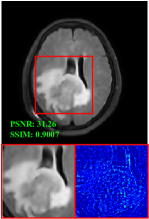

Figure 5 provides the qualitative comparison of the various methods on the four datasets at a scale of 4. The top, second, third, and bottom rows are the SR results under the FastMRI, clinical brain, clinical tumor and clinical pelvic datasets, respectively. The red boxes indicate the zoom-in region of complicated anatomical structures along with their corresponding error maps. Note that the brighter textures in the error maps, the lower the quality of the reconstructed images. As can be seen, compared to methods based on Transformers and CNNs, diffusion-based methods like DisC-Diff and DiffMSR (Ours) are capable of reconstructing high-realistic images with promising reconstruction metric scores (PSNR and SSIM). Nevertheless, while DisC-Diff can reconstruct high-precision MR images, it does not preserve the structure present in the original HR images, introducing some additional information that can affect medical diagnosis. In contrast, our method combines DM and PLWformer, which can preserve the original image’s structure while restoring high-frequency information.

In this section, we present more visual qualitative comparisons. Figures 8, 9, 10, and 11 show the reconstruction results of each method in FastMRI, clinical brain, clinical tumor, and clinical pelvic, respectively. As can be seen, although DisC-Diff can reconstruct MR images with high-frequency information, it fails to preserve the structure and content of the original Target HR image effectively, resulting in image distortion. In contrast, our proposed DiffMSR can restore high-frequency information while preserving the structure of the original HR image, indicating the effectiveness of the joint use of DM and PLWformer.